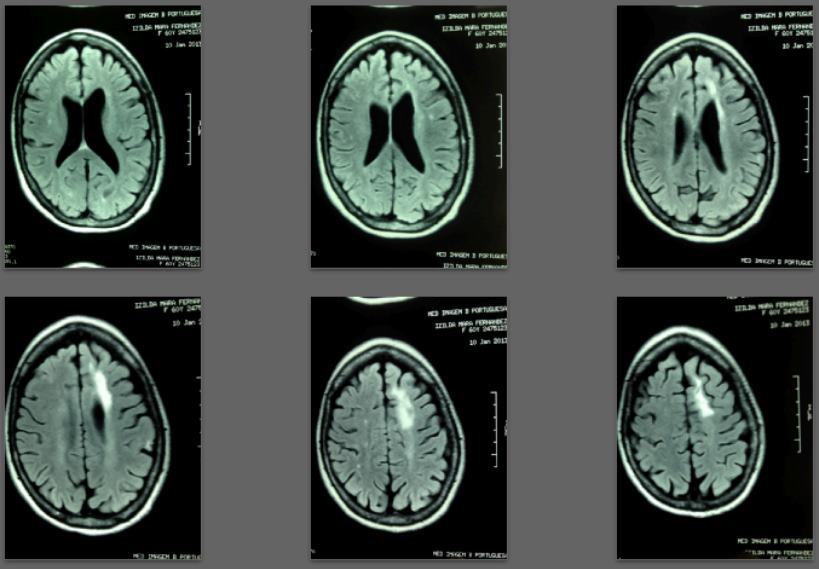

Specifically: Recent lesions appeared partially repaired or disappeared on MRI scans after one and two years of treatment.

Before/after MRI images for one of 1,000+ patients of Dr. Coimbra

PDF is attached at the bottom of this page

2008 Convulsive seizures Diagnosis: Balo’s concentric hemiparesis

Starting daily dose 25,000 IU; increased in stages to 80,000 IU on October 28, 2010. Asymptomatic since 2010.

2008 MRI